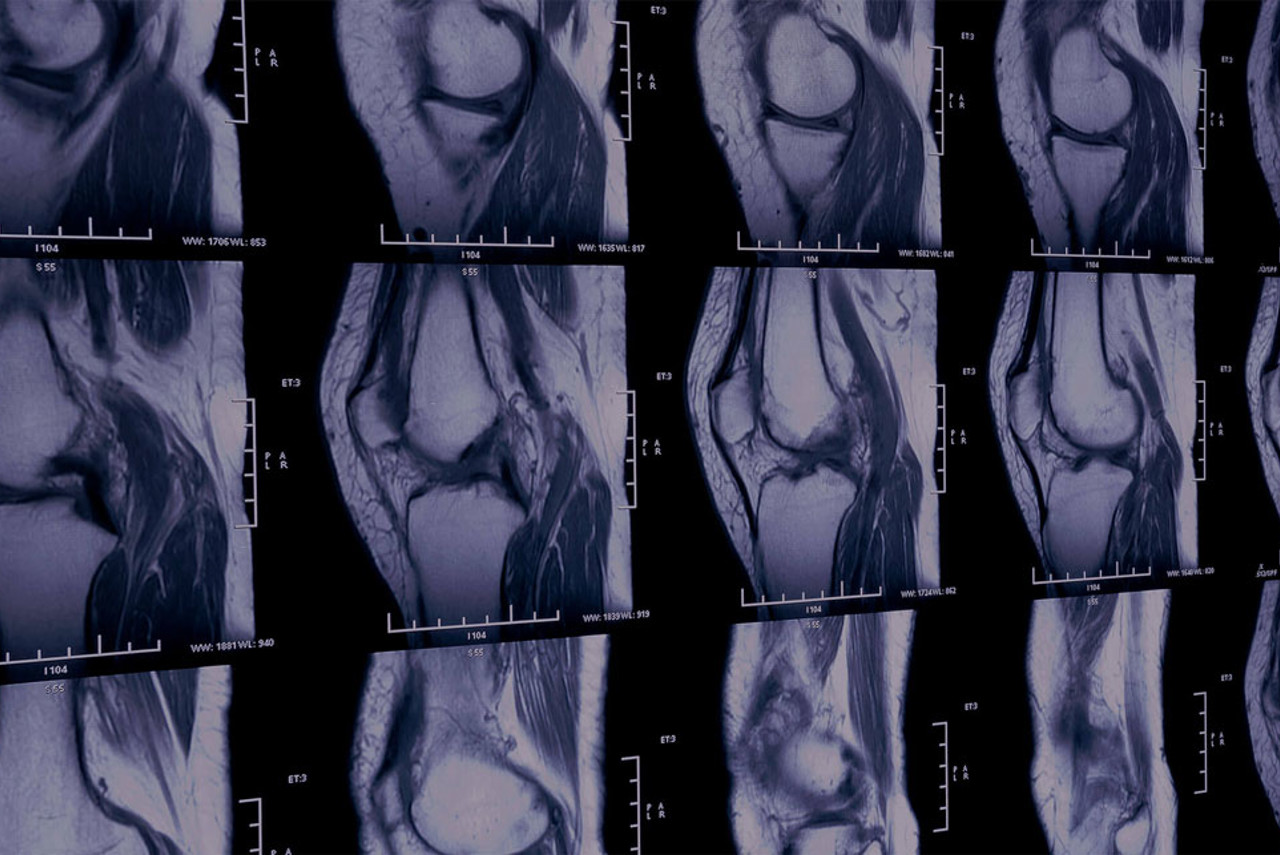

This scan can help diagnose various conditions, including tendonitis, bursitis, carpal tunnel syndrome, rotator cuff injuries, ligament tears, and joint problems. It’s also useful for identifying sports injuries or growths like cysts and tumours.

A warm gel will be applied to your skin, and the sonographer will use a small handheld device called a transducer to capture images.

The sonographer will gently press the transducer on your skin and move it over the area of interest, applying light pressure. You may also be asked to move the affected area during the scan to help reproduce symptoms and provide a clearer picture of how motion affects the area.